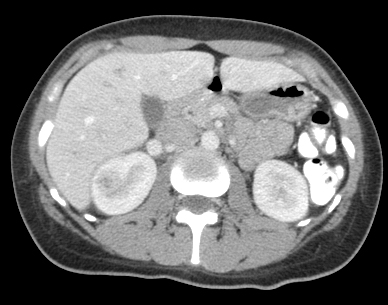

Diagnosis: acute focal nephritis. Also called focal lobar nephronia by rads. This is on spectrum somewhere between acute pyelonephritis and renal abscess. CT shown. Contrast image (not shown) demonstrated area of poorly perfused parenchyma without a cortical rim sign.